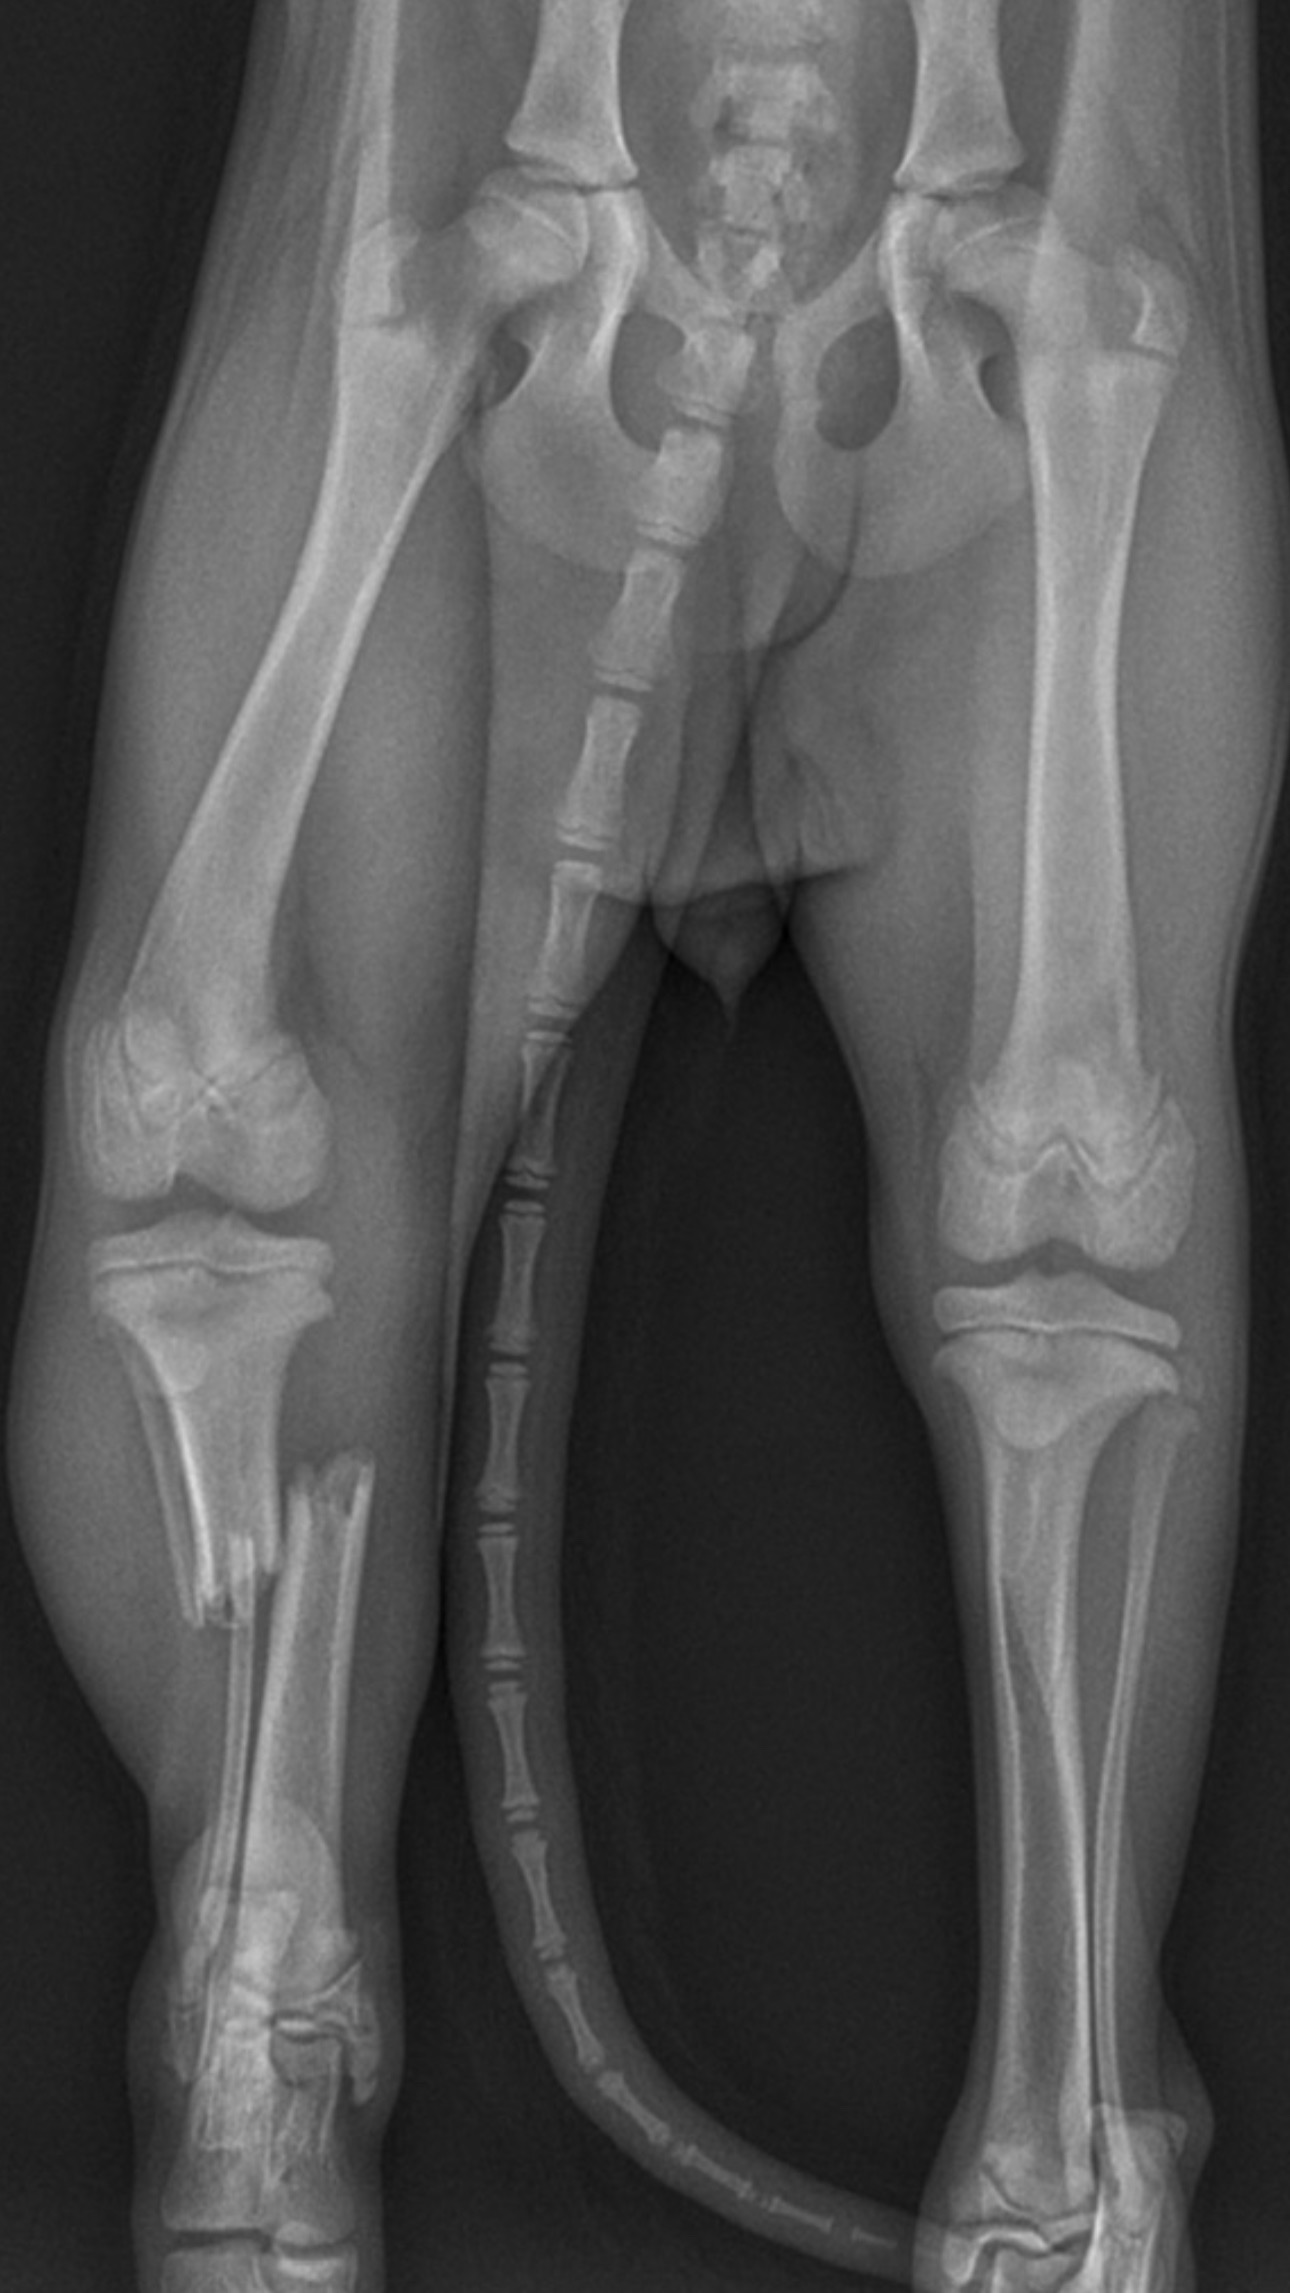

Yesterday I drove her almost 3 hours each way to VETSPR in Caguas. The X-rays are brutal: both bones between knee and ankle completely snapped.